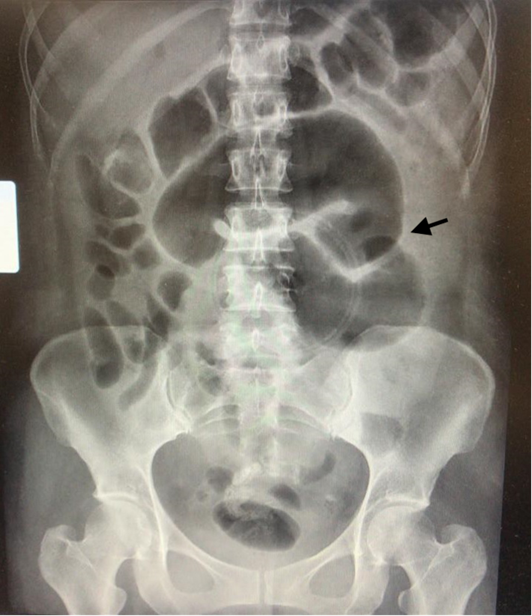

Foto 1 Radiografía simple de abdomen con evidencia de dilatación de asas intestinales. (Flecha señala la dilatación intestinal)

A la exploración física se observó pérdida de continuidad de 1 cm en la cicatriz previa, con secreción purulenta y dolor sin evidencia de irritación peritoneal. Se realizó radiografía simple de abdomen, (Foto 1) y tomografía de abdomen (Foto 2), ambas con datos sugestivos de oclusión intestinal; la tomografía documentó fístula enterocutánea, por fuga de medio de contraste a través de pared abdominal.